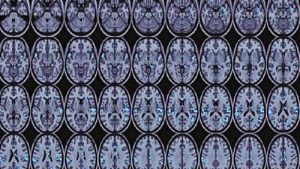

A newly published fMRI study conducted in New Zealand has confirmed that improved reading skills among dyslexic adults correspond with … Continue reading Research Confirms Right-Brained Dyslexic Reading Strength